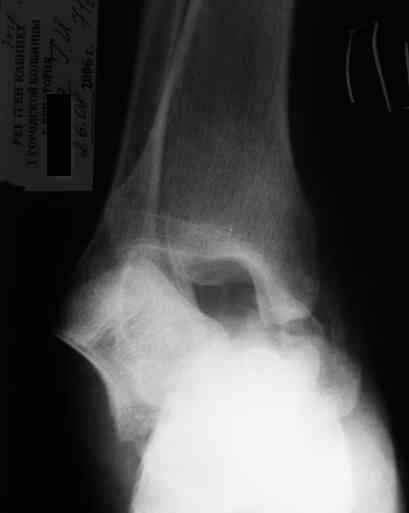

Уважаемый Александр! Как обещал представляю Р-граммы и операционные фото.

Ваши (лично ваши) рекомендации - астрагалэктомия-аппаратный пяточно-большеберцовый артродез с одновременным удлинением голени - правильно?

А удлинять голень в условиях плохих сосудов как? В смысле как потянутся склерозированные сосуды? Удлинять-то надо около 3 см.

При столь массивном секвестре (блок таранной кости), длительная антибиотикотерапия только губит естественную флору и помогает селекции

антибиотикоустойчивых штаммов.